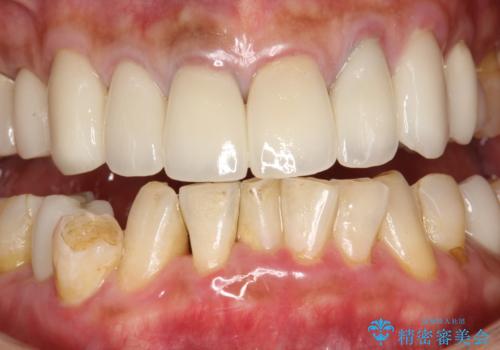

- 約1年ぶりの来院のため、着色や歯石がかなりついてしまっため、綺麗にしてほしいとのことでした。PMTC30分コースを行いました。

PMTC(保険外治療)は、毎日の歯磨きで落としきれない汚れや、コーヒ、紅茶などによる着色・タバコのヤニなどの着色も除去します。目には見えない歯と歯の間・歯肉の境目などに残っているプラーク(歯垢)もしっかり取り除きます。PMTCでは専門的な機械や材料を使用して、徹底的に汚れを除去するため、虫歯・歯周病・口臭予防などにつながります。